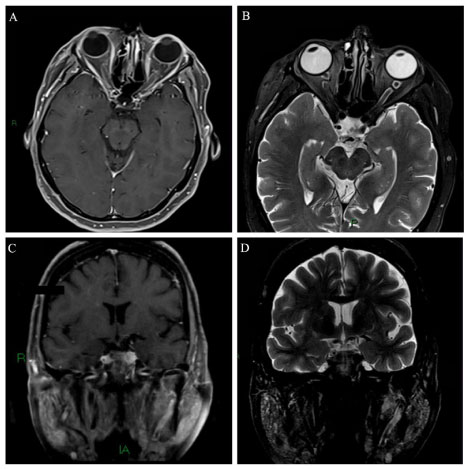

A 68-year-old woman started with a subacute onset of progressive visual acuity worsening associated with bilateral retrobulbar pain about 4 months ago. Fundoscopy was normal and reduced direct and consensual photo motor reflex. Sicca syndrome was confirmed in Schirmer test. Rheumatoid factor was positive (23.6) and anti-RO/LA antibody positive. Cranial MRI showed very thin and intense contrast enhancement along both optic nerve sheath and parotid edema associated (Figure 1) meeting the criteria of Sjogren syndrome (SS) [19]. We found no evidence of secondary SS suggesting a form primary.

Figure 1: Axial A) T1-spin echo, after gadolinium i.v. injection and axial; B) T2 with fat saturation show a very thin and intense symmetrically contrast enhancement along both optic nerve sheath as well a high intensity thickening along of both optic perineural CSF space. Coronal C) T1-spin echo, after gadolinium i.v. injection and coronal; D) T2 with fat saturation reveal a symmetrical increase of parotidite glands. View Figure 1